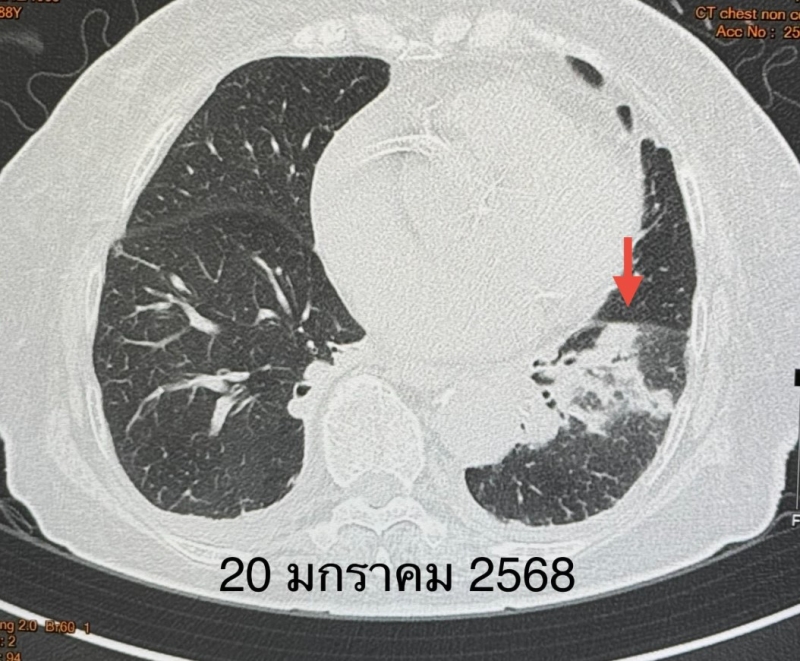

ตรวจร่างกาย ระดับออกซิเจนที่ปลายนิ้วต่ำ 87% ต้องให้ออกซิเจน 2 ลิตร/นาที ไม่มีไข้ ฟังปอดมีเสียงผิดปกติเล็กน้อยที่ปอดข้างซ้ายด้านล่าง เจาะเลือด เม็ดเลือดขาวในเลือดปกติ เอกซเรย์ปอดมีฝ้าขาวในปอดข้างซ้ายด้านล่าง ทำคอมพิวเตอร์ปอดยืนยันว่ามีฝ้าในปอดข้างซ้ายด้านล่าง และมีน้ำในช่องเยื่อหุ้มปอดเล็กน้อย ตรวจเลือดเม็ดเลือดขาวปกติ แยงจมูกส่งตรวจรหัสพันธุกรรมเชื้อ 22 สายพันธุ์ไม่พบเชื้อ ส่งเลือดตรวจ Legionella pneumophila Antibody IgM positive 1:200

วินิจฉัย : ติดเชื้อแบคทีเรียลีจิโอเนลลา นิวโมฟิลา Legionella pneumophila ทำให้ปอดอักเสบ ให้ยา azithromycin และ levofloxacin คนไข้ดีขึ้น ไม่ไอ ไม่เหนื่อย ระดับออกซิเจนปกติ ไม่ต้องใช้ออกซิเจน วันที่ 26 มกราคมเอกซเรย์ปอดกลับมาเป็นปกติ